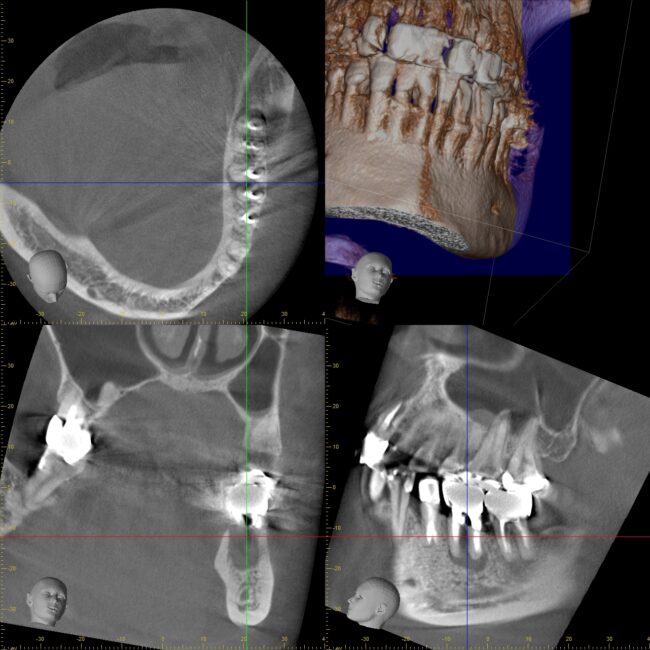

専門医が行う根管治療① 3DCTの有用性 〜宇部市歯医者(歯の神経の...